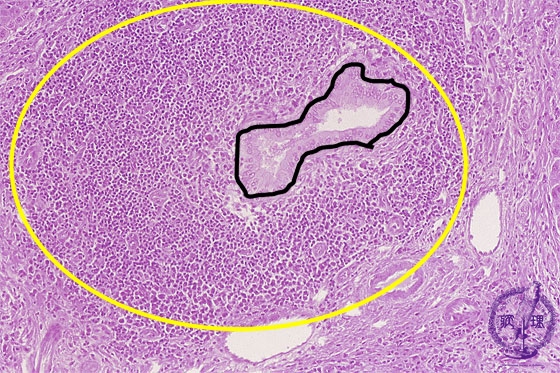

- 10.Liver

- (4)Primary biliary cirrhosis

Microscopic image (HE stain, intermediate power): There is a marked lymphocytic infiltrate (yellow circle) around bile ductules (image, center ・ black dot) within expanded portal areas and the bile ductular epithelium is damaged. These changes are characteristic of chronic non-suppurative cholangitis.

Click the image to see the enlarged image.